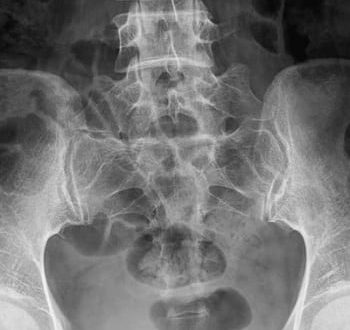

Диагностика дисплазии тазобедренных суставов После того как дома вы самостоятельно выявили признаки дисплазии тазобедренных суставов у ребенка, врач направит вас к ортопеду. Опытный специалист может на осмотре определить степень заболевания и назначить…

Что такое дисплазия? За диагнозом скрывается нарушение в развитии хрящевой тканей, в основном оно развивается во время внутриутробного формирования плода. Другое наименование дисплазии – врожденный вывих бедра. Фактически…